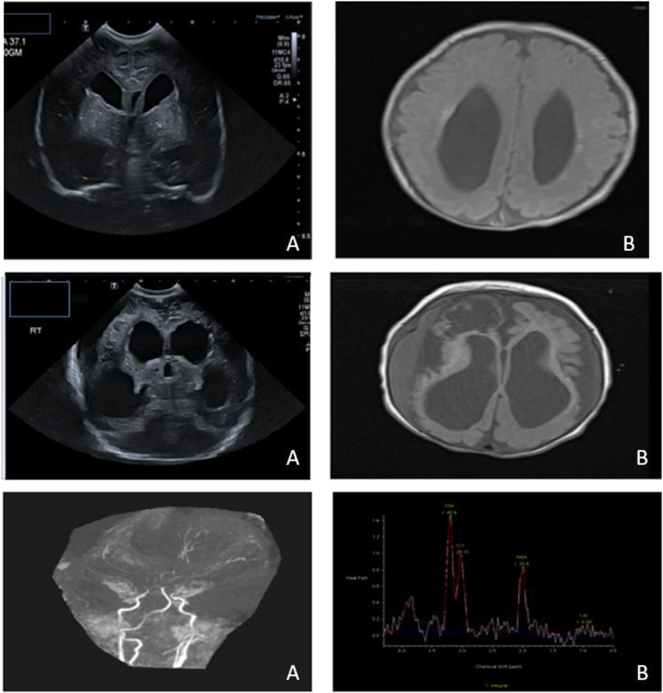

Case presentation: A male term neonate presented with antenatal ventriculomegaly and early fetal growth restriction. He was dysmorphic at birth and his postnatal course was complicated by transient myeloproliferative disorder, neonatal seizures, skin rash, conjugated hyperbilirubinemia, and milk protein allergy. Etiological work-ups including congenital infections, immunological disorders, and inborn error of metabolisms were negative. The findings of transient myeloproliferative disorder in association with partial 1q trisomy which have not been previously described in the literature, raise the possibility of abnormal vasculature of generalized nature, resulting in cutis marmorata, signs of intestinal inflammation, and abnormal cerebral vascular supply.